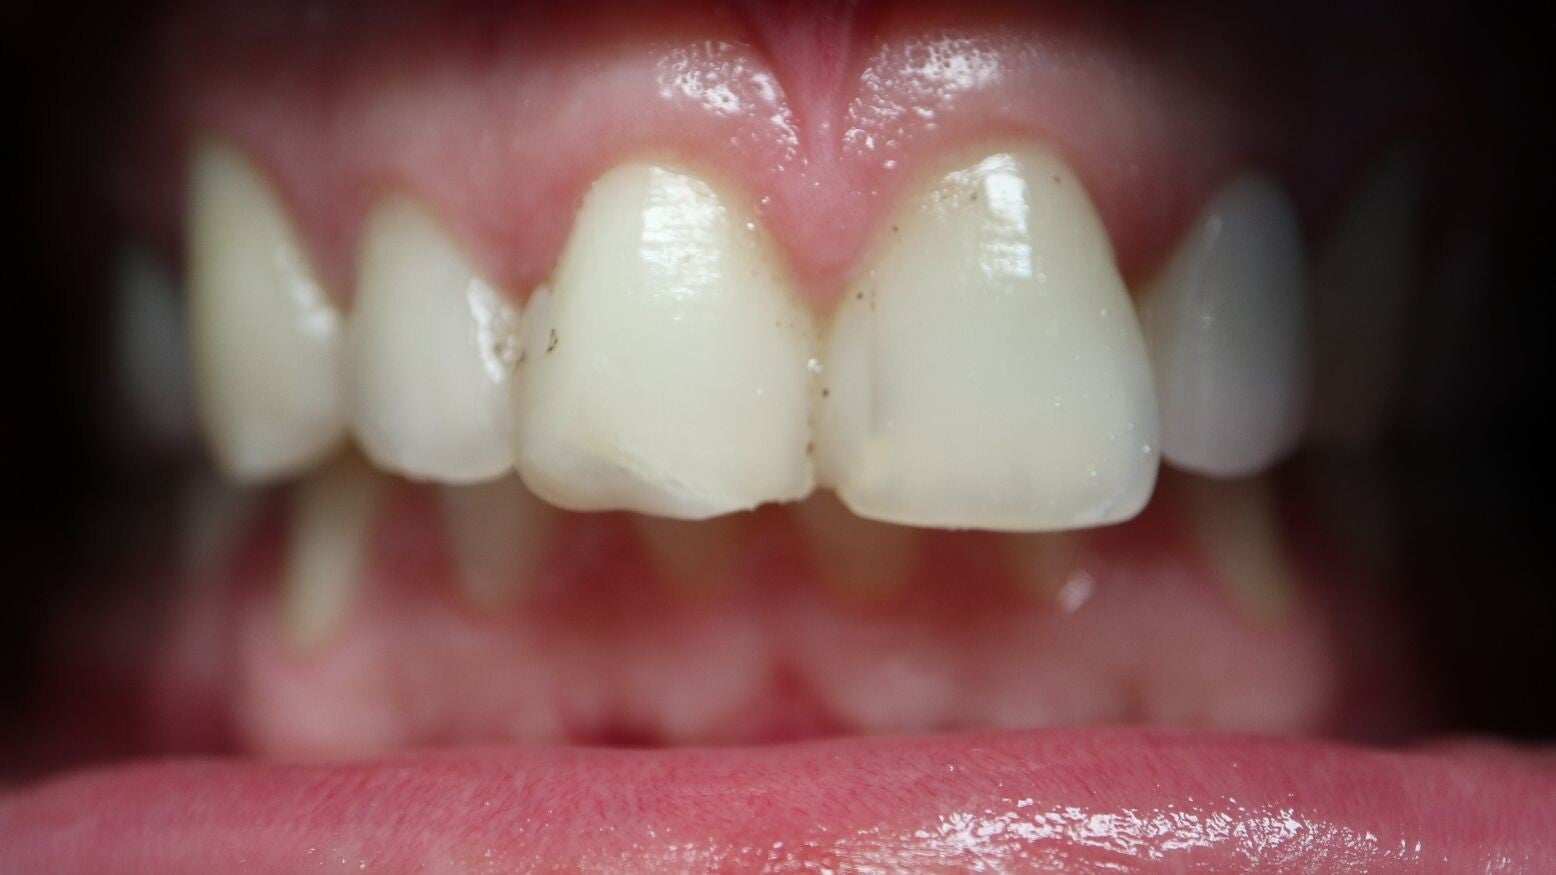

Supraclusion

Les incisives du haut recouvrent complètement les incisives du bas